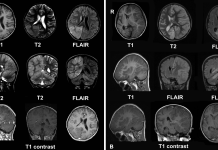

Review for MS drug Zinbryta after cases of inflammatory brain disorders

The European Medicines Agency (EMA) has commenced an urgent review of the multiple sclerosis (MS) medicine Zinbryta, following cases of serious inflammatory brain disorders.

There...